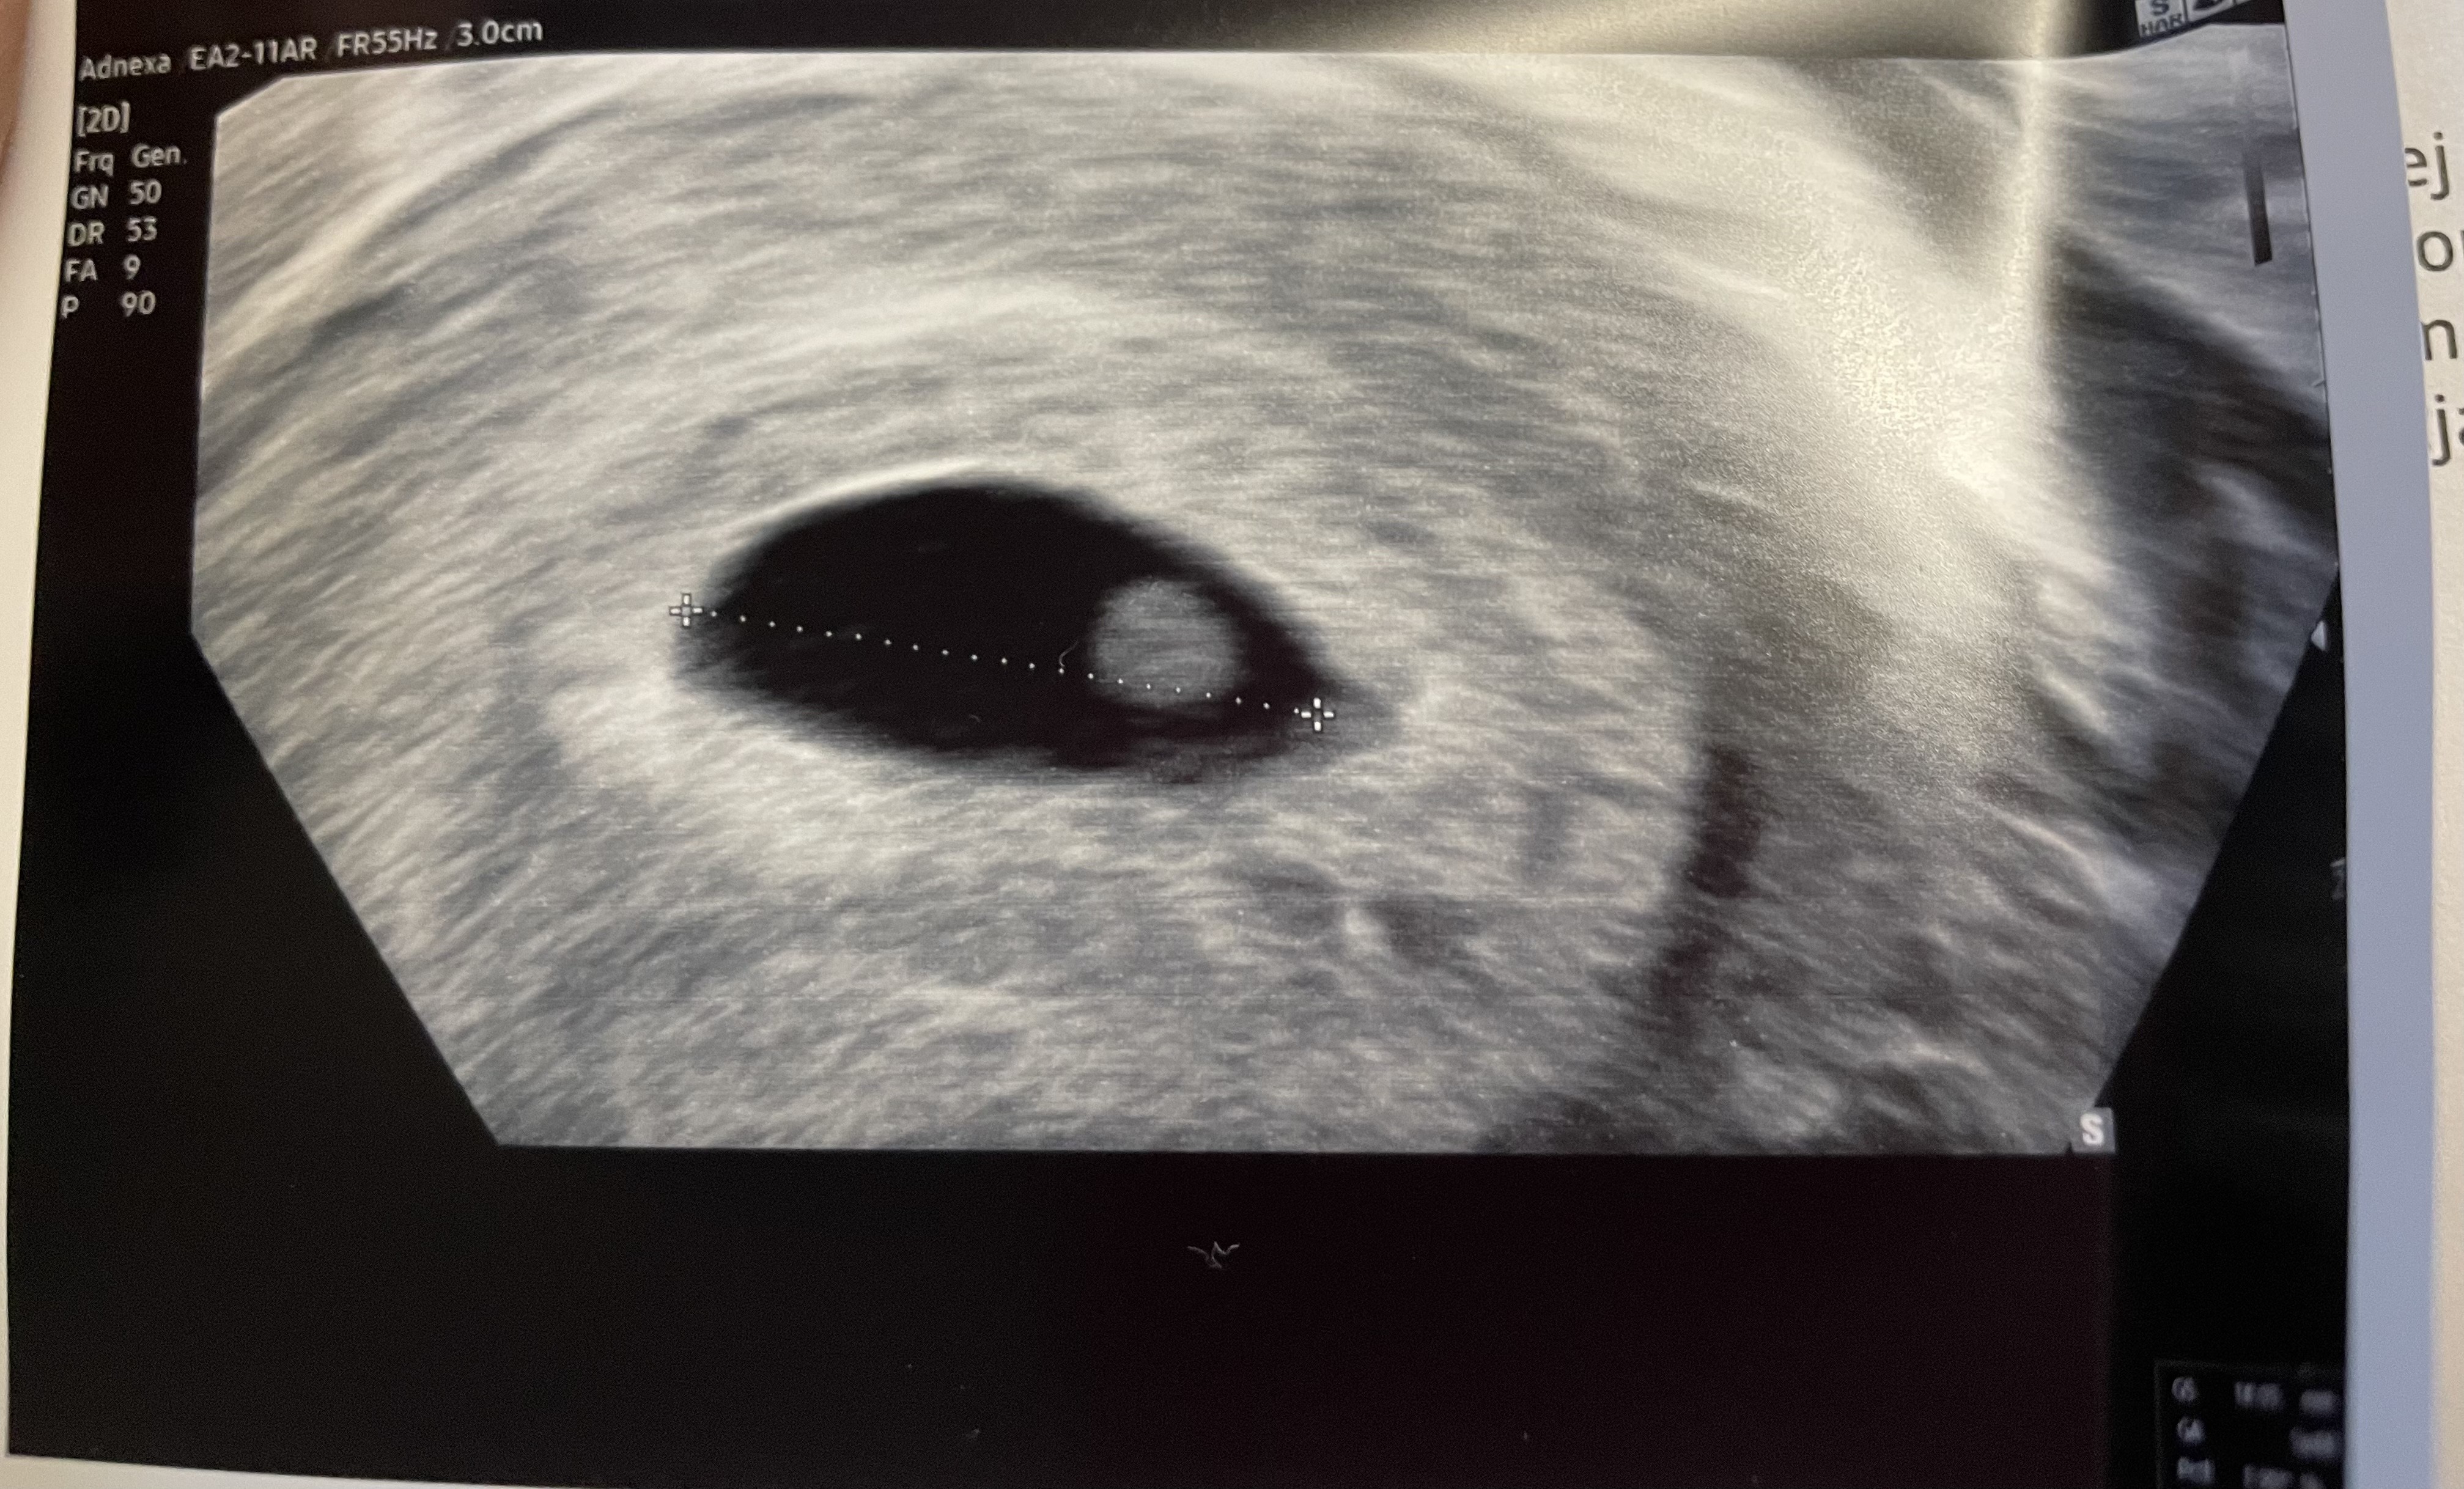

PIĘKNE WIEŚCIZarodek 2,6mmjeszcze bez serduszka.

Z USG wychodzi 5+5 wg pani ginekolog, według OM 5+2, ale wpisała mi termin porodu z okresu

W środę idę na NFZ, mam nadzieję, że zobaczę serduszko na walentynki![]()

super wieściZarodek 2,6mmjeszcze bez serduszka.